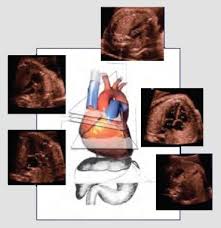

El ventrículo derecho fue bipartito en el 30 por ciento, unipartito en el 6 por ciento and tripartito en el 64 por ciento de los casos. Se identificaron anormalidades coronarias en el 36 por ciento, y circulación de estas dependiente del ventrículo derecho en el 7,1 por ciento. La mediana para el valor del anillo valvular tricuspideo fue de -3. El diagnóstico fue hecho en etapa fetal en seis de 28 casos (21.4 por ciento). Se tomaron las medidas para que en todos estos pacientes el parto se produjera, en un hospital cercano al centro cardiovascular.

La reparación quirúrgica se realizó, basándose en predictores ecocardiográficos, el grupo con solución biventricular mostró un valor Z tricuspideo promedio de -1,1 para el grupo univentricular este valor fue de -5 (p<0,001), el índice trucúspide/mitral (T/M) fue de 0,8 y 0,4 respectivamente (p<0,001). Tres pacientes dentro del grupo biventricular requirieron, posteriormente una solución de tipo ventrículo y medio con un índice T/M medio de 0,4 (p<0,001). Existió 100 por ciento de concordancia respecto a la presencia de alteraciones coronarias, entre las técnicas ecocardiográficas y angiográfica. Este estudio muestra datos acerca de la diversidad morfológica, los esfuerzos iniciales en el diagnóstic fetal, hecho en nuestro país, además de los excelentes resultados quirúrgicos obtenidos con un enfrentamiento diagnóstico y terapéutico selectivo, en esta poco común patología (AU)